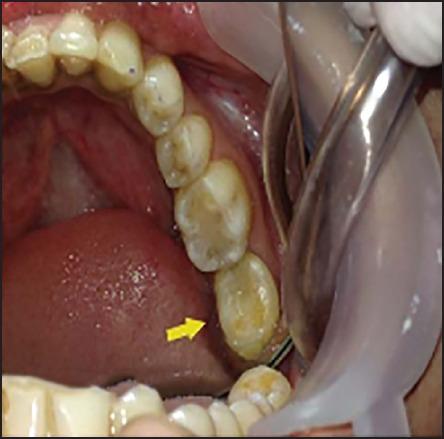

Autogenous tooth transplantation refers to the repositioning of autogenous teeth in another tooth extraction site or a surgically formed recipient site to replace missing teeth due to congenital deformity, grossly decayed carious teeth, mobile teeth due to periodontal disease, teeth lost due to trauma, endodontic failure or any other reason when a suitable donor tooth is available. This is a case report of autotransplantation of impacted #38 with complete root formation into the extraction site of grossly decayed, unrestorable #37 with 18 months follow-up showing excellent periapical healing and tooth stability. In autogenous tooth transplantation, even if the donor's tooth has complete root formation, a high success rate can be achieved if the cases are selected and treated properly. Chances of root resorption are there because of necrotic pulp and periodontal irritation during manipulation. However, autogenous tooth transplantation should always be considered as a good treatment modality in feasible cases.

自体牙移植是指将自体牙重新植入另一牙齿拔除部位或手术形成的受植部位,以替代因先天性畸形、严重龋坏、牙周病导致的松动牙、外伤缺失牙、牙髓治疗失败或其他任何原因导致的缺失牙,前提是有合适的供体牙。本文报告一例将牙根完全形成的阻生38号牙自体移植至严重龋坏、无法修复的37号牙拔除部位的病例,随访18个月显示根尖愈合良好且牙齿稳固。在自体牙移植中,即使供体牙牙根已完全形成,若病例选择和治疗得当,仍可获得较高成功率。操作过程中因牙髓坏死和牙周刺激,存在牙根吸收的风险。然而,在可行的病例中,自体牙移植应始终被视为一种良好的治疗方式。